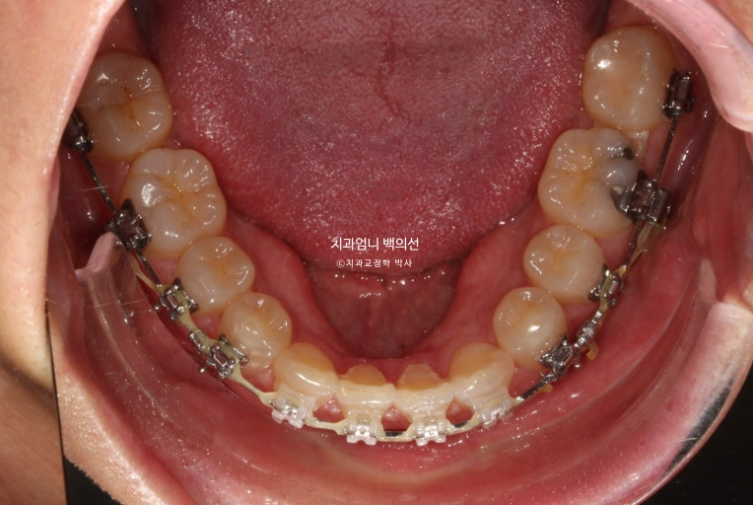

24.07

치료시작 10개월째 모습입니다.

상악 발치공간이 보입니다.

아래는 송곳니를 앞니자리로 끌어오는 중입니다.

환자분이 30대임에도 치아이동속도가 빠른 편이였고